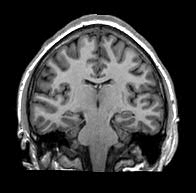

Right Mesial Temporal Sclerosis (MTS)

Also, see arrow in figure at the top of the page.